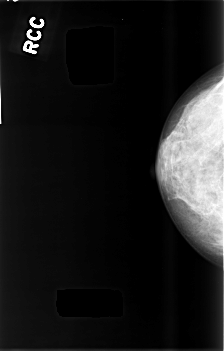

C_0482_1.RIGHT_CC

RIGHT_CC LINES 4552 PIXELS_PER_LINE 2912 BITS_PER_PIXEL 12 RESOLUTION 50 NON_OVERLAY